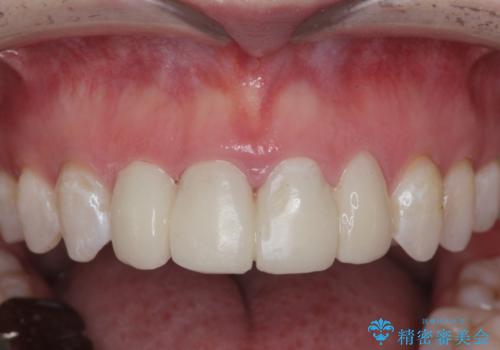

仮歯のまま放置していた前歯をセラミックに

- 仮歯のまま放置してしまい、変色を改善しきれいなセラミッククラウンをいれたい、と希望され来院されました。

特に虫歯の再発や神経の症状等問題を認めなかったので、審美的に優れるセラミッククラウンに仮歯を置き換えていきます。

- 52.8万円(ジルコニアクラウン×4・仮歯×4)費用は治療当時の料金となります